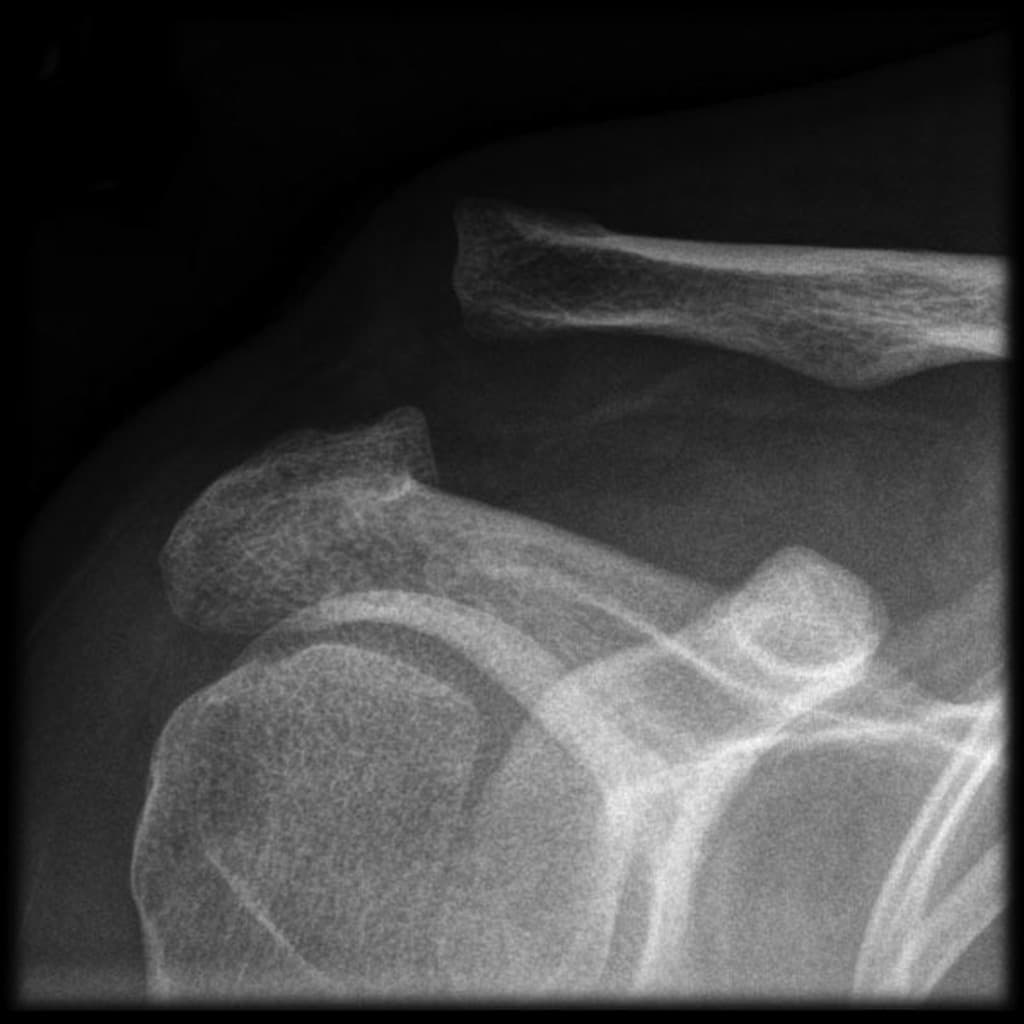

- Thấy một mấu xương nhỏ mọc ra ở bờ trong xương vai, có lớp sụn che phủ dày khoảng 4,5 mm.

- Mấu xương bất thường ở bờ trong xương vai, có lớp sụn mỏng che phủ, phù hợp với u sụn xương (osteochondroma) – phát hiện tình cờ.

Rockwood Classification System of Acromioclavicular Joint Injuries (Hệ thống phân loại Rockwood các tổn thương khớp cùng đòn)

Acromioclavicular Joint Injury - Type III (Chấn thương khớp cùng đòn - loại III)

Acromioclavicular Joint Dislocation with Tightrope Fixation (Trật khớp cùng đòn với cố định bằng Tightrope)

Rockwood Classification of Acromioclavicular Joint Injury (Phân loại Rockwood tổn thương khớp cùng vận động)

Acromioclavicular Joint Dislocation (Trật khớp cùng đòn)

Acromioclavicular Joint Injury with Superior Clavicle Displacement (Chấn thương khớp cùng đòn)